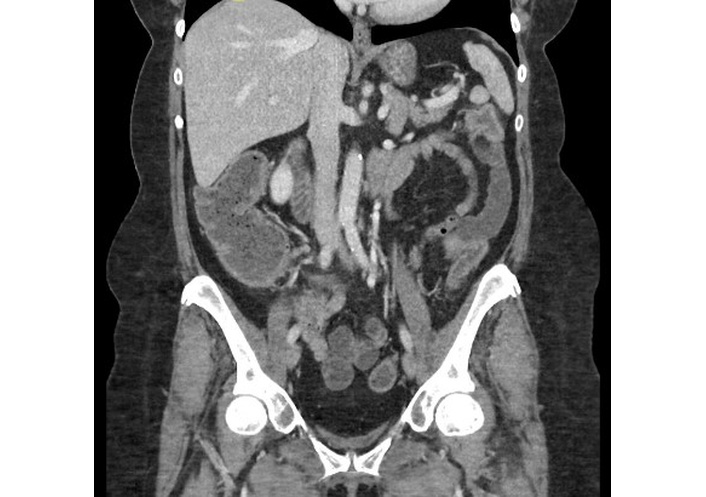

Seven days after the endoscopy, the patient presented to her local emergency department with progressively worsening symptoms. Upon presentation, the patient was tachycardic (heart rate 105 bpm), dehydrated, and exhibited mild lower abdominal tenderness. Laboratory tests revealed ALB 2.9 g/dL, HGB 9.8 g/dL, and a negative Clostridioides difficile PCR. Abdominal and pelvic computed tomography (CT) in the emergency department demonstrated fluid-filled small bowel loops with mild circumferential wall thickening involving the splenic flexure and descending colon (Figure 2). She was admitted to general surgery with internal medicine consultation and was started on intravenous (IV) methylprednisolone 125 mg daily, along with PO budesonide 9 mg daily and PO mesalamine 4 g daily. After a negative infectious workup, PO loperamide was started for diarrhea. The patient’s abdominal pain worsened, and IV morphine and PO ibuprofen were ordered.

Coronal contrast-enhanced CT of the abdomen and pelvis demonstrates mild mucosal hyperenhancement with adjacent inflammatory stranding and edema involving the splenic flexure and descending colon. CT: computed tomography.